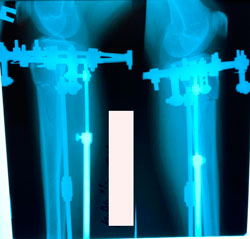

рентген перед фиксацией

image-05-01-21-06-30-6.jpg

image-05-01-21-06-30-8.jpg